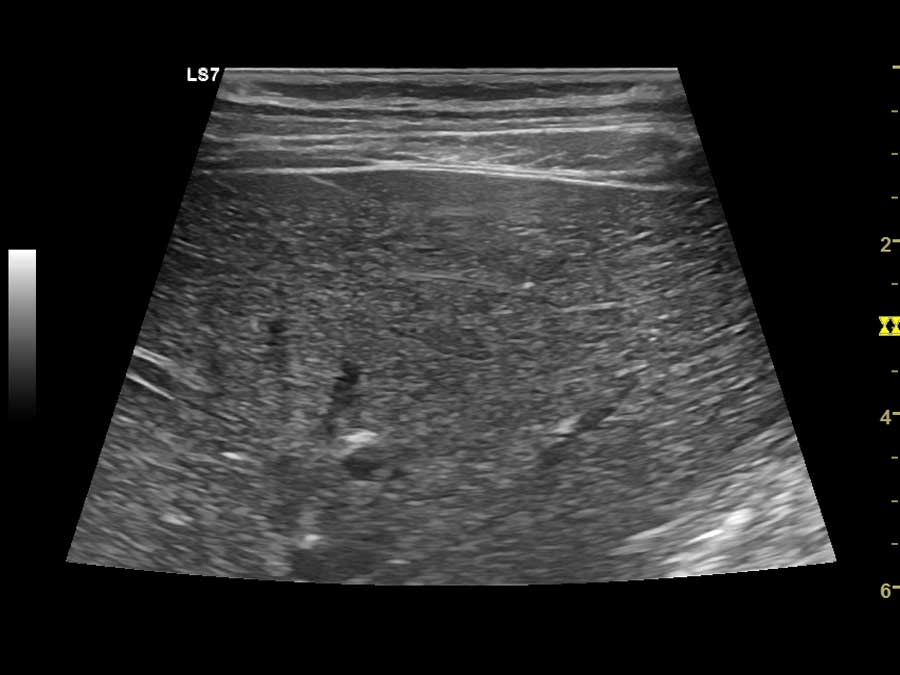

- Υπερηχογράφημα ήπατος, χοληφόρων, παγκρέατος, σπληνός, νεφρών, επινεφριδίων, ουροδόχου κύστης